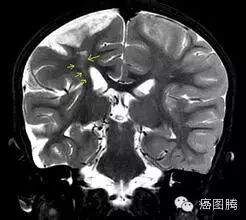

兴奋性中毒(Excitotoxicity)谷氨酸酯及其类似物质等神经递质的过度刺激,使神经细胞受损及死忘的病理过程;